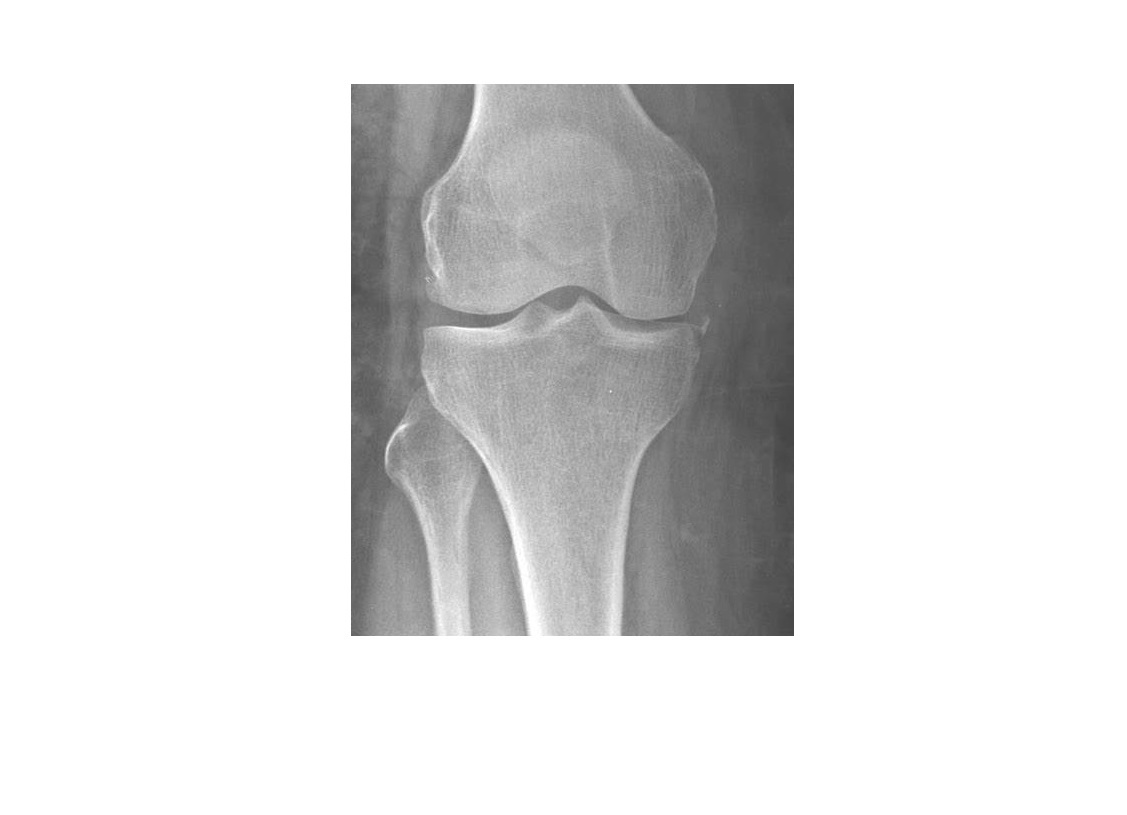

Segond fracture

Lateral tibial plateau

Associated with ACL tear (75%) and internal rotation